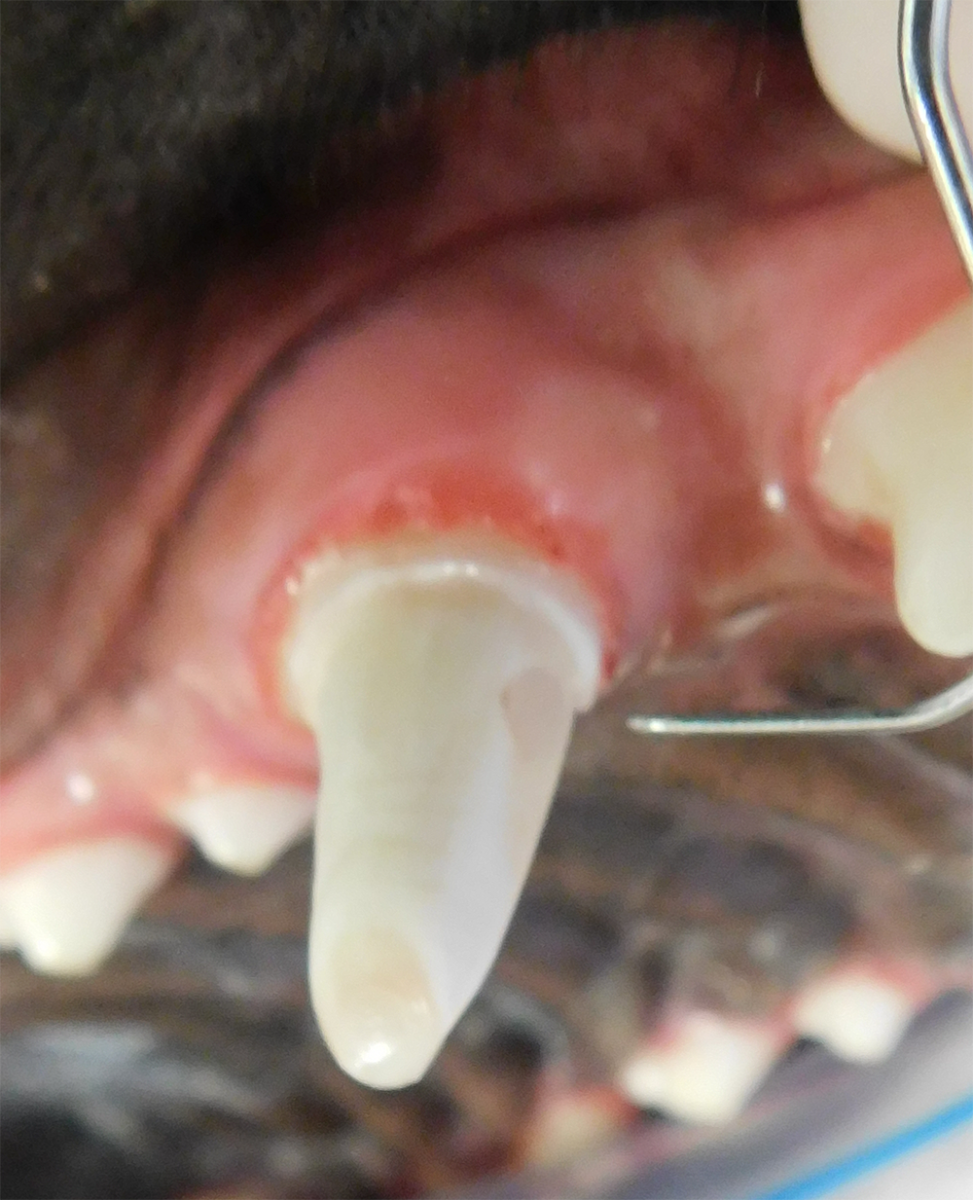

Periodontal disease is extremely common in dogs and cats. Over 80% of dogs and cats over two years of age have some degree of periodontal disease. Periodontal disease is best prevented by yearly professional dental cleanings starting at two years of age and at home brushing at least three times weekly. Brushing should begin at a very early age to allow your new pet to get used to regular brushing. In severe cases of infection or periodontal disease, the teeth may need to be surgically extracted. Extractions should always involve x-rays of the tooth first, as many teeth have multiple roots or may be diseased below where the eye can see. Extracting larger teeth in animals requires oral surgery, equivalent to removing wisdom teeth in people. It is vital that all of the tooth and roots be removed for the periodontal infection to resolve. In cases of important teeth with mild to moderate periodontal disease, multiple periodontal treatments can be offered to help save these teeth.